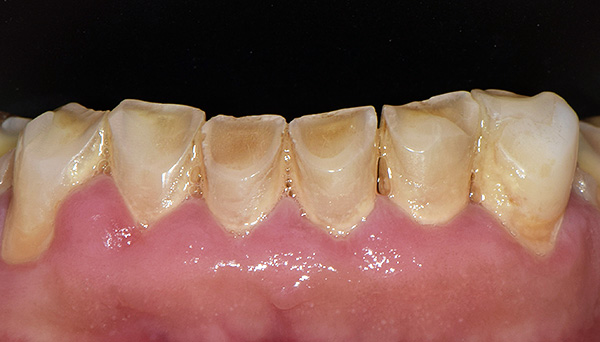

La foto sotto mostra ciò che provoca l'abrasione dei denti a causa di un'occlusione impropria nella regione anteriore:

Normalmente, i denti laterali delle mascelle superiore e inferiore non devono rimanere sullo stesso piano quando sono chiusi. Cioè, i molari devono avere una certa inclinazione, in modo che con vari movimenti della mascella inferiore, i denti laterali non perdano il contatto tra loro. In presenza della corretta inclinazione dei denti, si formano linee tracciate condizionatamente - curve occlusali: